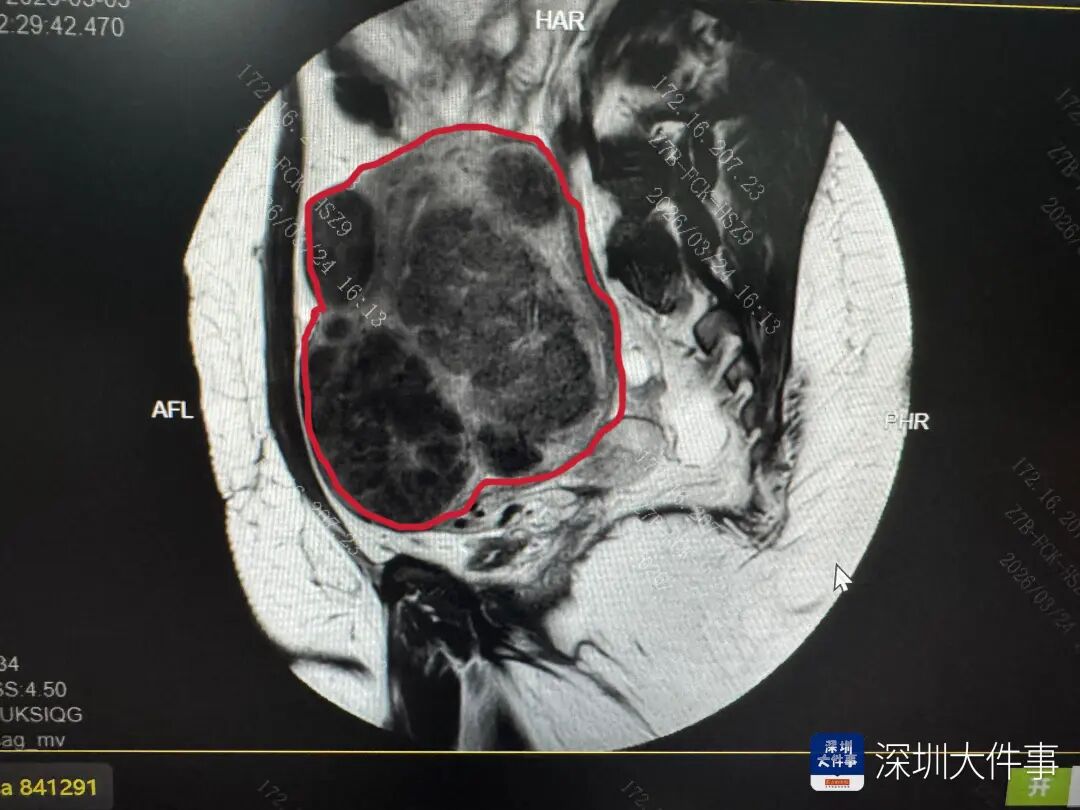

安娜的手术堪称高难度挑战的集合:她体重达216斤、臀围128cm,皮下脂肪厚导致手术视野暴露困难;子宫被肌瘤撑至孕4个月大小,形态完全失常;肌瘤最大直径超10cm,最小的肉眼几乎不可见;加之有既往腹腔镜肌瘤剔除术伴大出血病史,盆腔存在广泛致密粘连,解剖结构完全紊乱。

手术中,团队先耐心分离盆腔广泛粘连,再从宫底到宫颈、从浆膜层到粘膜层开展“地毯式”排查,精准剥离每一颗肌瘤,同步完成子宫肌层结构修复重建,全程规避关键组织器官损伤风险。经过5小时的精细操作,团队顺利完成手术,共剔除可计数肌瘤656颗,足足装满两个托盘。